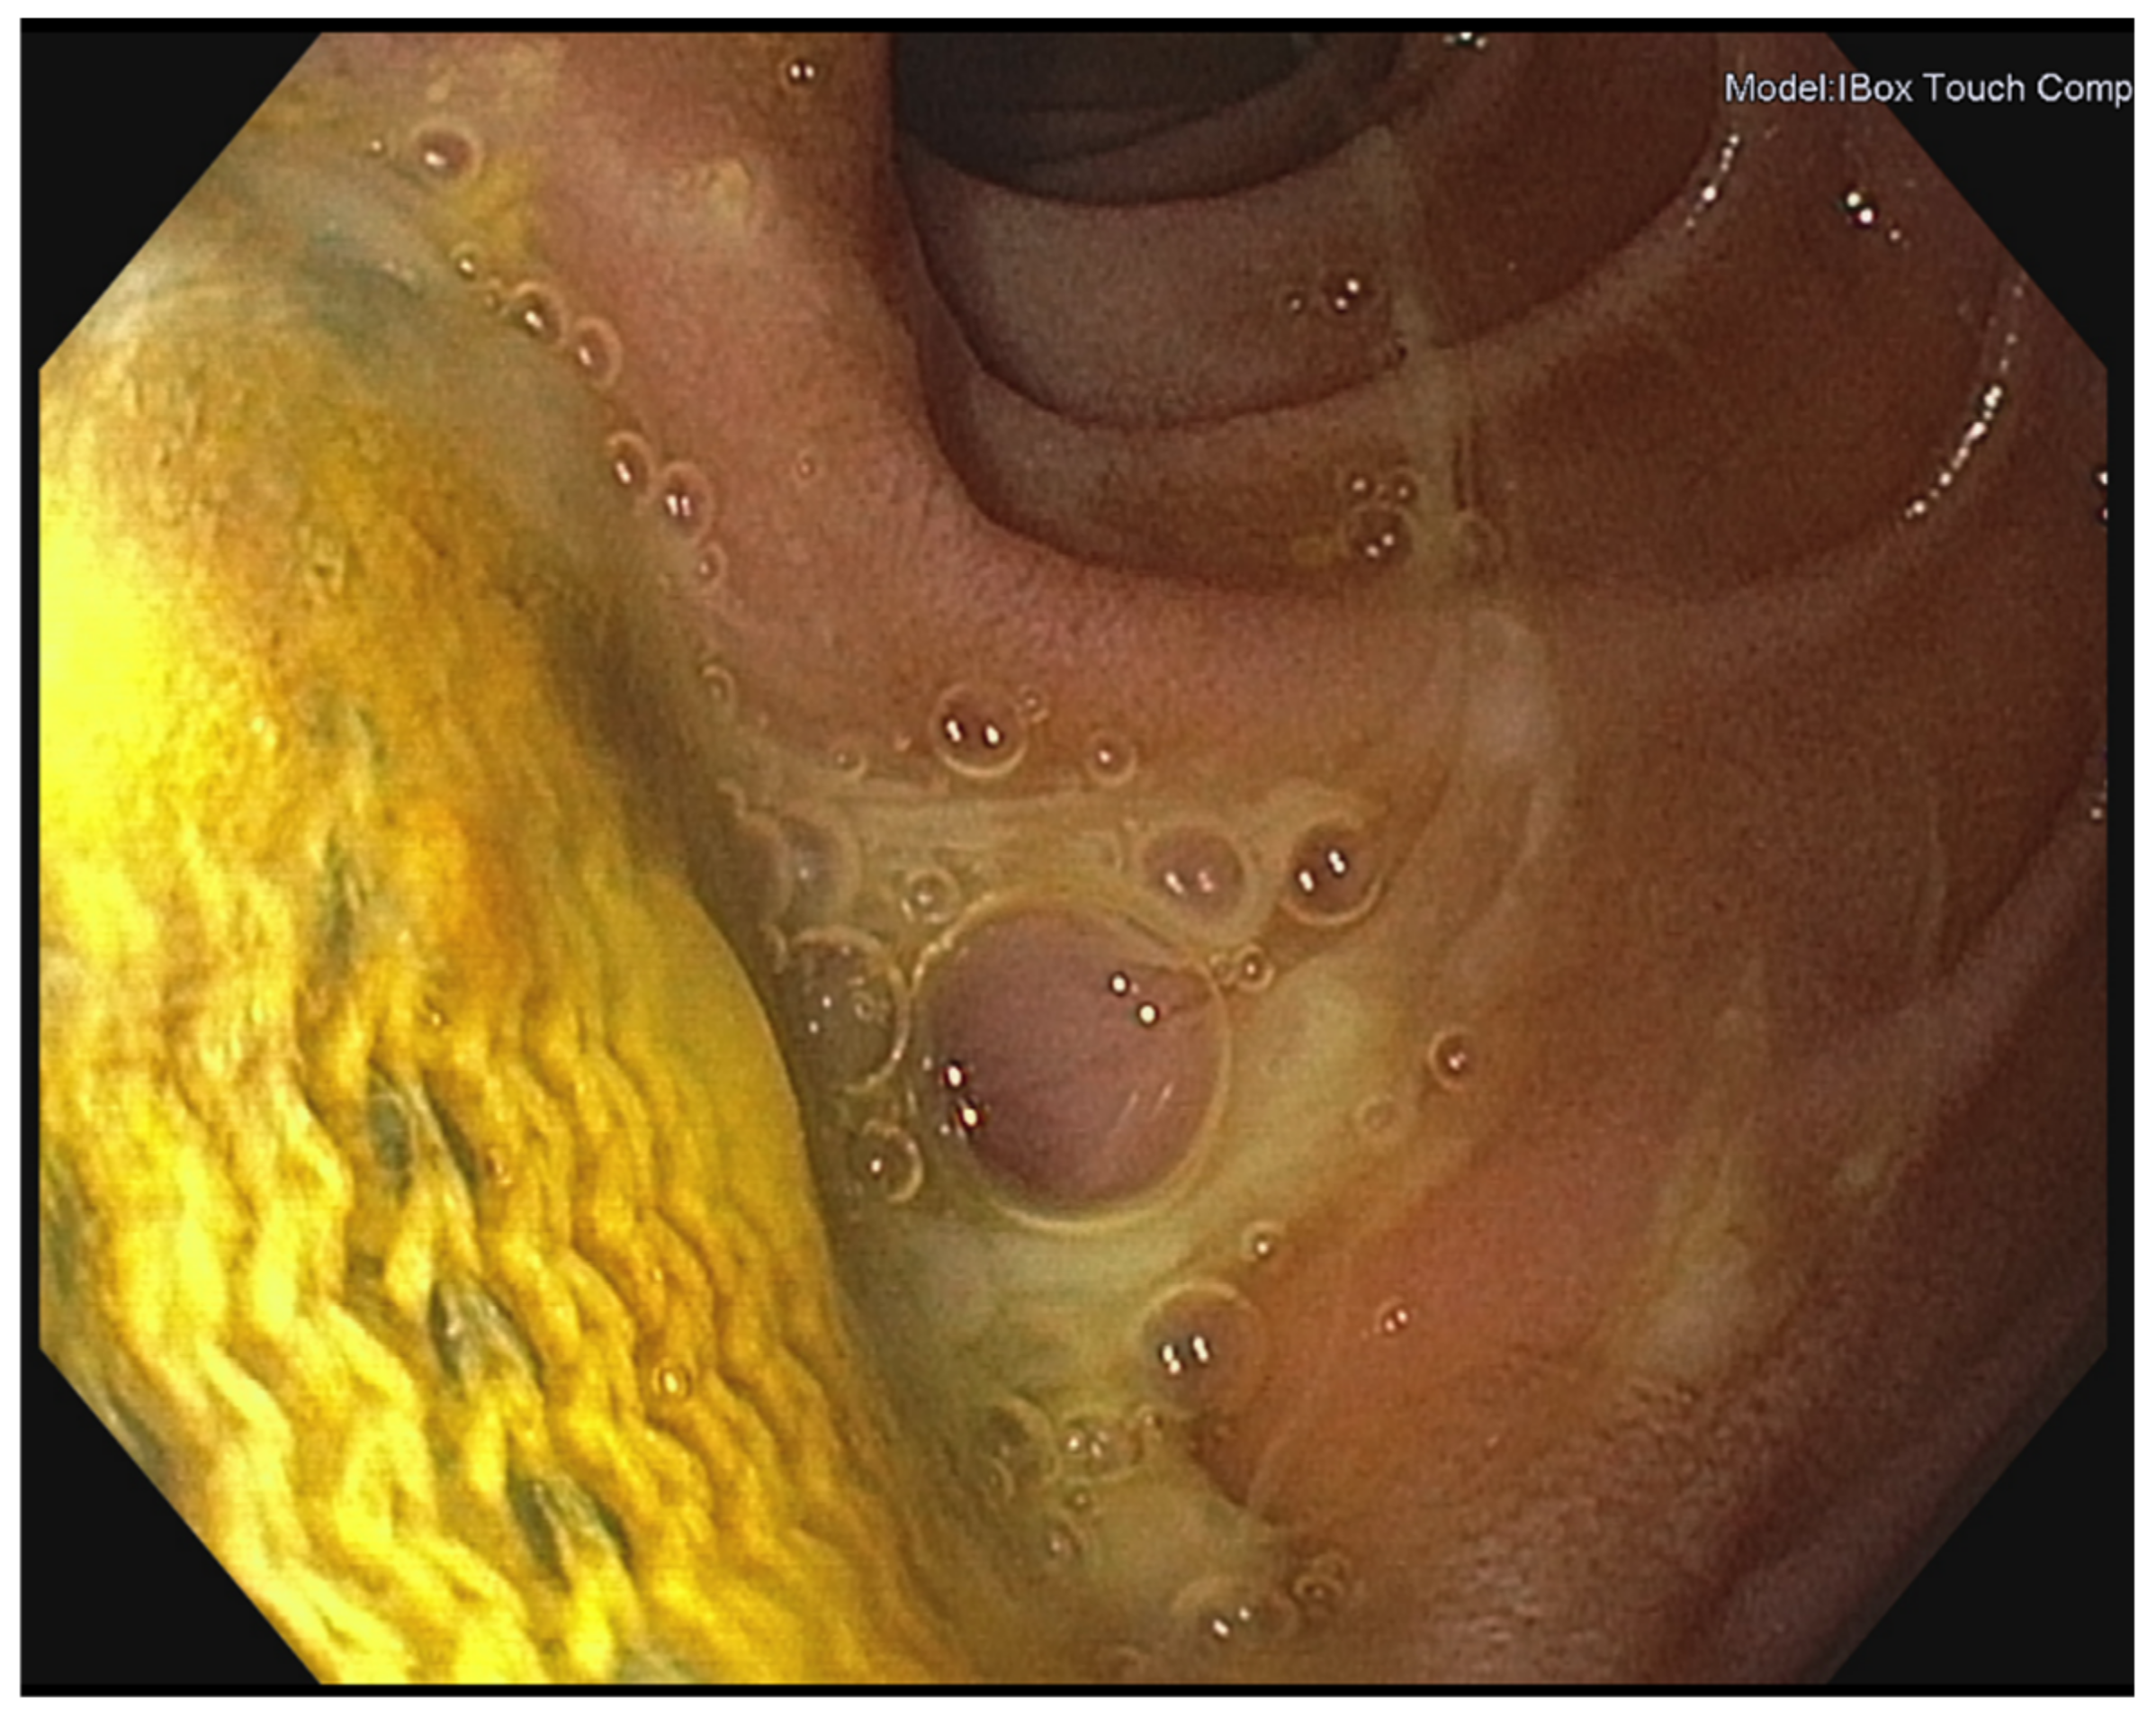

2.2. Presentation-Diagnosis-Management

3.2. Presentation-Diagnosis-Management